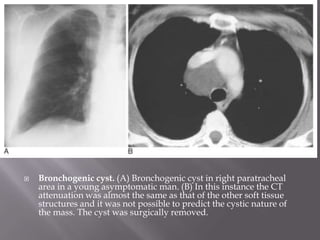

 Bronchogenic cyst. (A) Bronchogenic cyst in right paratracheal

area in a young asymptomatic man. (B) In this instance the CT

attenuation was almost the same as that of the other soft tissue

structures and it was not possible to predict the cystic nature of

the mass. The cyst was surgically removed.